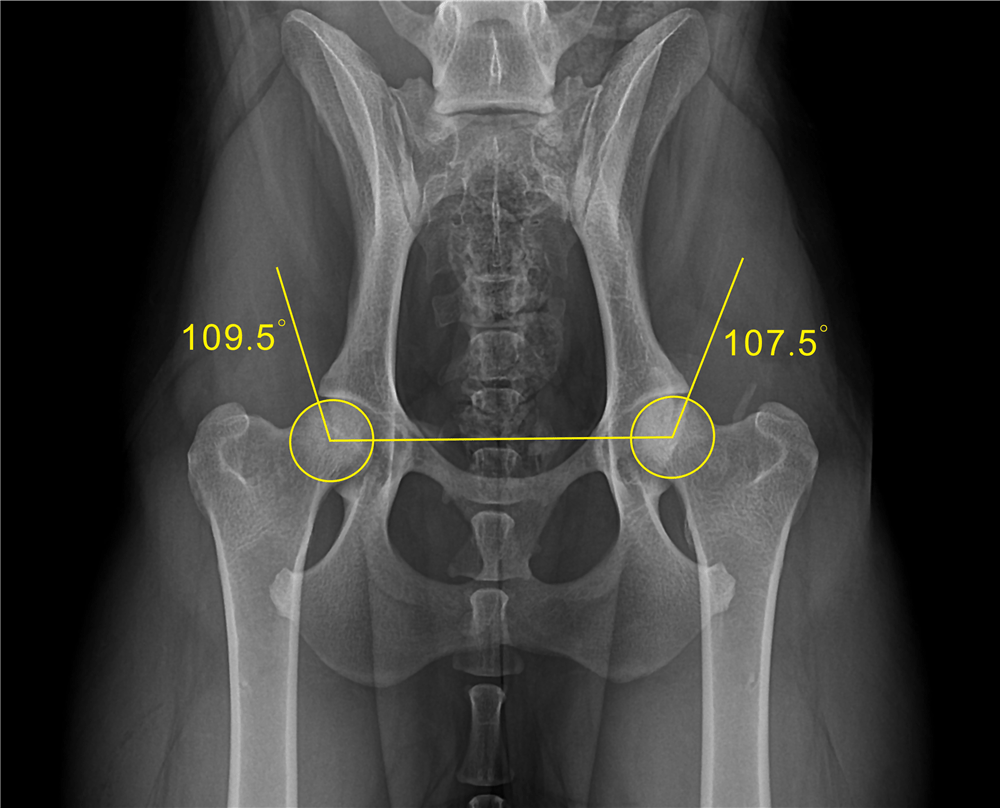

Hip Dysplasia Dog Norberg Angle . Hip dysplasia is the most common orthopedic condition of the dog, causing joint inflammation and secondary osteoarthritis, which lead to variable degrees of clinical discomfort. The angle between these lines is the. The norberg angle and the percentile rank accurately discriminated between dogs with or without canine hip dysplasia, with positive and negative likelihood ratios of 6·31 and. Then take the center of the femoral head and draw a line to the outer point of the pelvis. 66 genetically, it is a disease of complex inheritance, meaning that multiple genes, combined with environmental influences, ultimately cause expression of the condition. Extended hip and abducted hind limb radiographs performed at 1 year of age (18 months for large breed dogs) are scored according to the official. The norberg angle and the percentile rank accurately discriminated between dogs with or without canine hip dysplasia, with positive and.

Measurement of the Norberg angle in the extended view. Download Hip Dysplasia Dog Norberg Angle Extended hip and abducted hind limb radiographs performed at 1 year of age (18 months for large breed dogs) are scored according to the official. The norberg angle and the percentile rank accurately discriminated between dogs with or without canine hip dysplasia, with positive and negative likelihood ratios of 6·31 and. 66 genetically, it is a disease of complex inheritance,. Hip Dysplasia Dog Norberg Angle.

Image Diagnostic Software SuperXvue® DXR superveterinary Hip Dysplasia Dog Norberg Angle The norberg angle and the percentile rank accurately discriminated between dogs with or without canine hip dysplasia, with positive and negative likelihood ratios of 6·31 and. Extended hip and abducted hind limb radiographs performed at 1 year of age (18 months for large breed dogs) are scored according to the official. Hip dysplasia is the most common orthopedic condition of. Hip Dysplasia Dog Norberg Angle.

Image Diagnostic Software SuperXvue® DXR superveterinary Hip Dysplasia Dog Norberg Angle The angle between these lines is the. Hip dysplasia is the most common orthopedic condition of the dog, causing joint inflammation and secondary osteoarthritis, which lead to variable degrees of clinical discomfort. Extended hip and abducted hind limb radiographs performed at 1 year of age (18 months for large breed dogs) are scored according to the official. Then take the. Hip Dysplasia Dog Norberg Angle.